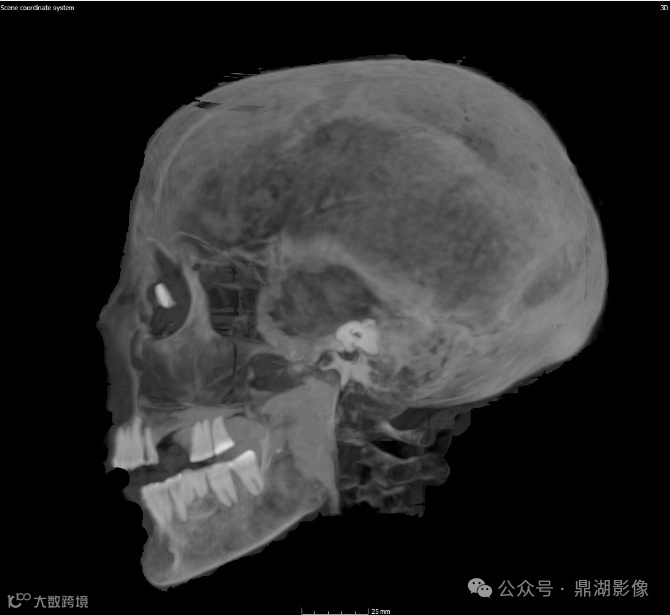

颅脑图像

现在可以断定她去世时的年龄为30多岁或40岁出头;

她失去了几颗牙齿,剩余牙齿严重磨损,这表明她吃的食物中含有对牙釉质有损害的散沙颗粒;

扫描结果还显示,Chenet-aa夫人的眼窝中还植入了辅助眼球。